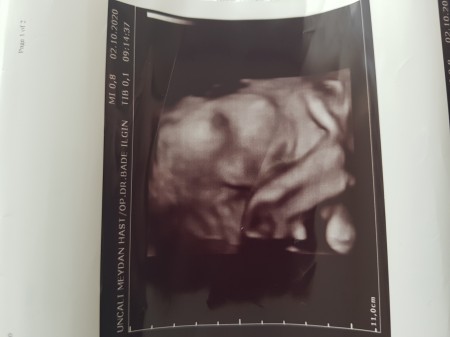

Misafir 26 mayıs 2020 salı 14 56 37 haftalık hamileyim bebeğim bugün hiç hareket etmedi neden aceba. Etiketler 37 1 gebelik 37 hafta 37 haftalik bebek 37 haftalık bebek gelişimi 37 haftalık bebek görüntüsü 37 haftalık bebek hareketleri 37 haftalik dogan bebek 37 haftalık doğan bebek yaşarmı 37 haftalık doğan bebekler 37 haftalık gebelik 37 haftalık gebelikte bebek hareketleri 37 haftalık hamileyim 37. Hafta gebelik anne. Yorum yazmak için üyelik girişi yapmalısınız.